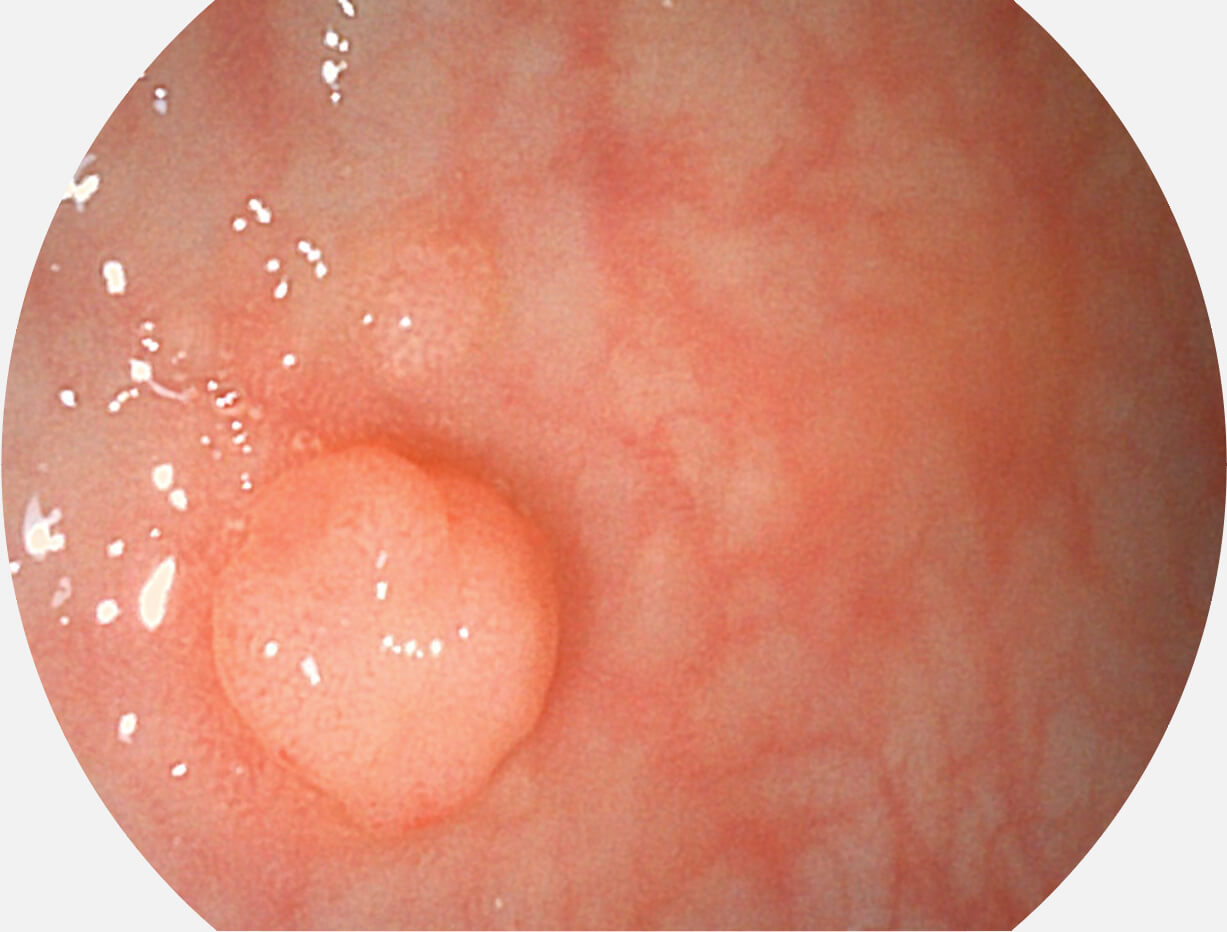

Versatile Intelligent Staining Technology, VIST

强调浅层黏膜结构的同时,保证照明亮度和提升浅层微血管与中层血管颜色对比度,病变边界更清晰。

VIST图像